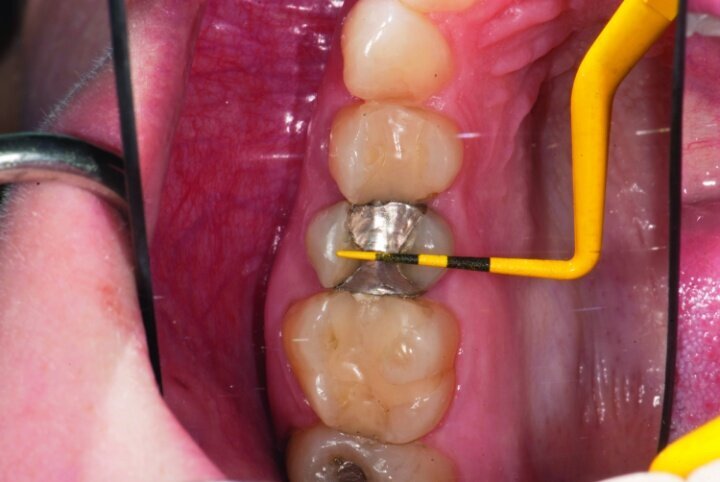

After gross occlusal reduction was completed, the remaining enamel ring was measured (Figs. 9a, b). The enamel rings were noted to be 1.5 mm, and the teeth were prepared for adhesively retained restorations. If the enamel rings were less than 1 mm, the teeth would have been prepared on the axial walls to create retention for cohesively retained crowns.

The remainder of the existing composite resin in #3 and the amalgam in #4 were removed. The occlusal surfaces of the preparations were blended into the interproximal areas using a KS2 bur to create smooth preparations (Figs. 10–15c). There was no retention or resistance form prepared to retain the restorations.